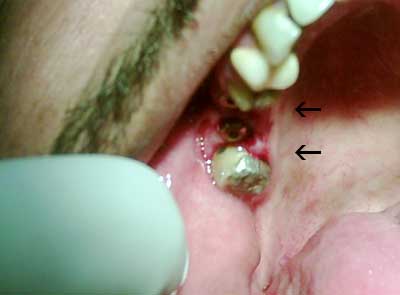

في اليوم التالي تمت زراعة 7 زرعات سويسرية خلال ساعتين وأنا لم أشعر بأي ألم خلال الزراعة لأنه بالواقع أسهل كثير من الذي كنت أتوقعه ، هو فقط خدر اللثة وزرع .